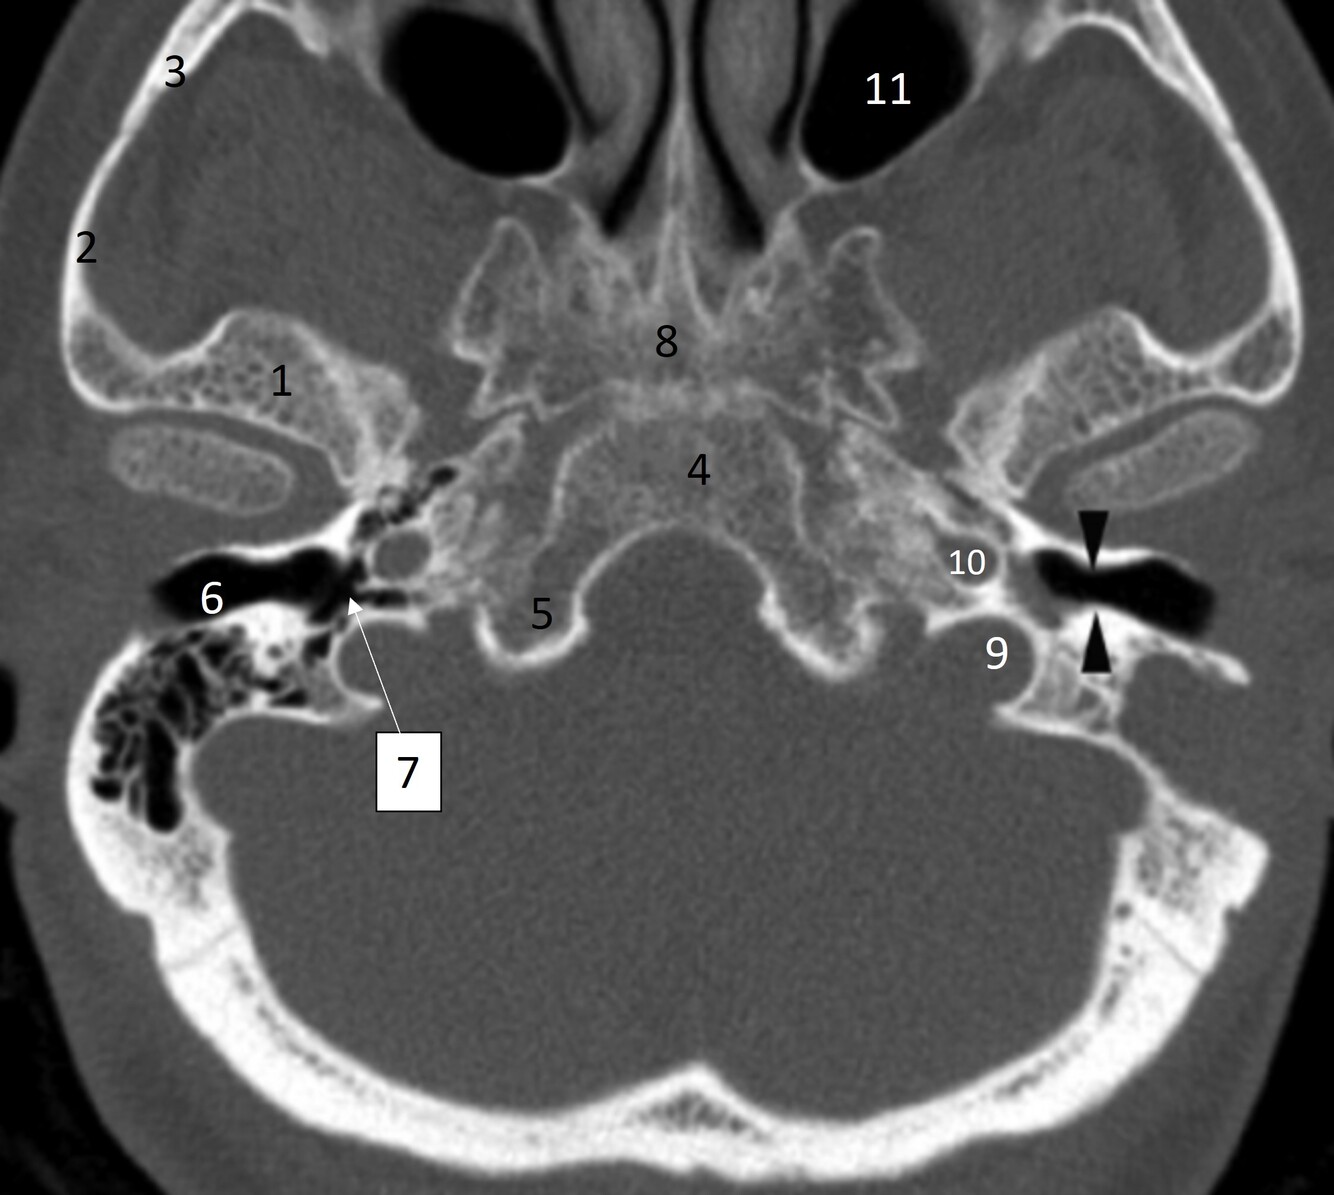

20

Label 36,37,46,62

36=Rt. Inferior nasal concha

37=Lt. Inferior nasal meatus

46=Lt. carotid canal

62= Lt. EAM

22

Q

What narrowing are the black arrowheads pointing at?

A

Isthmus of Rt EAC

5=Occipital bone

6=Rt EAC

24

Label 7-11

7-Rt middle ear/tympanic cavity

8=Sphenoid

9=Lt jugular foramen

10.=Lt carotid canal

11=Lt maxillary sinus